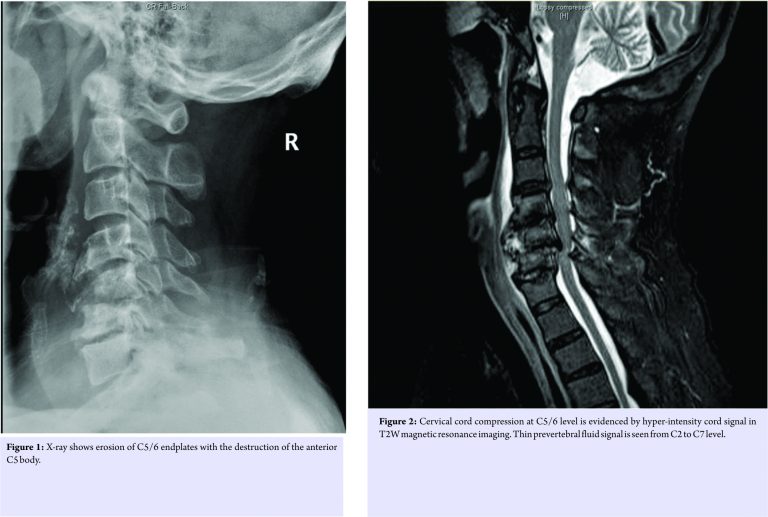

A 66-year-old man was admitted through emergency department for neck pain, bilateral upper limbs weakness and clumsiness for 1 week. He has a history of Type 2 diabetes mellitus, hypertension and chronic renal insufficiency. He is a chronic drinker. He was febrile on presentation. Physical examination revealed bilateral upper limb weakness with muscle power of Medical Research Council (MRC) Grade 4/5. Hoffmann’s sign was positive, and there was presence of reverse supinator jerk and brisk upper limbs reflexes. Laboratory tests revealed leukocytosis (white cell count 10.5 × 109 /L), elevated C reactive protein level (7.7 mg/L), and elevated creatinine level (222 umol/L) which was similar to his baseline level. X-ray of the cervical spine showed loss of disc height at C5/6 level with adjacent endplate erosions and C5 vertebral body destruction (Fig. 1). In view of suspected C5/6 infective spondylodiscitis, contrast computed tomography (CT) and plain magnetic resonance imaging (MRI) of the cervical spine were performed. On the contrast CT scan, in addition to the bony erosions evident on X-ray, a thin layer of prevertebral fluid was present from C2 to C5 level. No rim enhancing collection was seen. The plain MRI scan showed moderate cervical spondylosis. The cervical cord was also shown to be moderately impinged between the posteroinferior margin of C5 vertebral body and C6 lamina with mild focal myelomalacia changes (Fig. 2). Overall, clinical and radiological features were suggestive of infective spondylodiscitis with resultant cervical myelopathy.